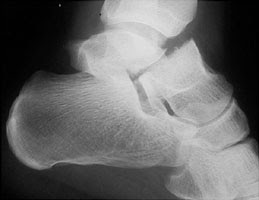

2

Q

Describe this fracture?

A

AVIATOR

- Vertical fracture of talar neck with subtalar dislocation and backward displacement of body

- via forced dorsiflexion of foot